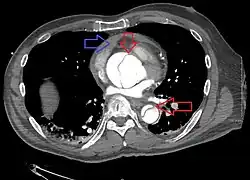

Computed tomography

Computed tomography angiography is a fast, noninvasive test that gives an accurate three-dimensional view of the aorta. These images are produced by taking rapid, thin-cut slices of the chest and abdomen, and combining them in the computer to create cross-sectional slices. To delineate the aorta to the accuracy necessary to make the proper diagnosis, an iodinated contrast material is injected into a peripheral vein. Contrast is injected and the scan performed using a bolus tracking method. This type of scan is timed to an injection to capture the contrast as it enters the aorta. The scan then follows the contrast as it flows through the vessel. It has a sensitivity of 96 to 100% and a specificity of 96 to 100%. Disadvantages include the need for iodinated contrast material and the inability to diagnose the site of the intimal tear.

-

Aortic dissection -

CT with contrast demonstrating aneurysmal dilation and a dissection of the ascending aorta (type A Stanford) -

Chest CT with descending (type B Stanford) aortic dissection (red circle)

Type A dissection with pericardial effusion as a result.